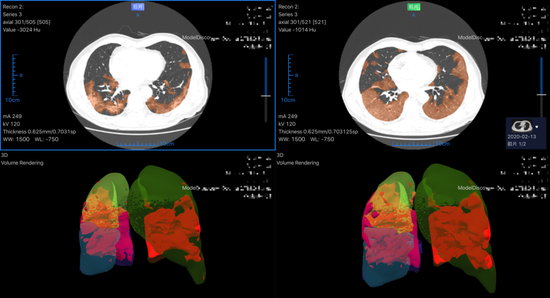

据数坤科技马春娥介绍,这款产品同样能在2~3秒内识别炎性病灶、分割定位,勾画感染区域,对病灶区域进行量化评估。

该系统的随访功能更受徐良洲的青睐,尤其在新增病例减少、收治患者复查日益增多的窗口期。“以往至少需要15分钟的对比,计算机两三分钟就可以把它做完。”